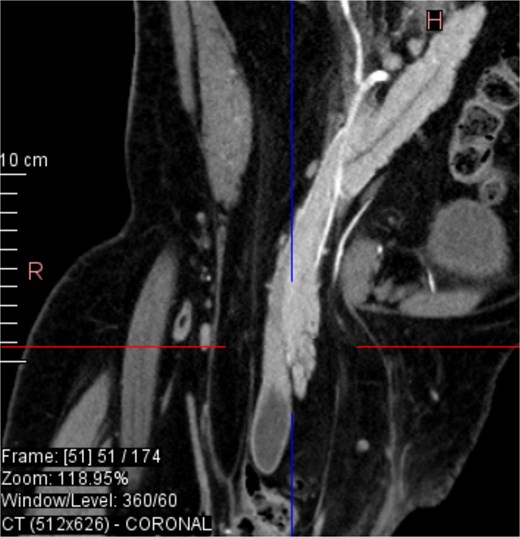

CT imaging (Figs 2–5) revealed a right inguinal hernia containing small bowel loops, ascending colon, the second and third portions of the duodenum, and the pancreatic head. The pancreatic head appeared rotated and displaced inferiorly into the hernia sac, without signs of acute pancreatitis.

Sagittal CT view inguinal hernial sac with pancreatic head and D2 and D3 segment of duodenum.

Additionally, incidental findings (Fig. 2) included multiple calculi within the left hepatic duct. Though the patient was asymptomatic from a hepatobiliary standpoint, the presence of these stones raised concern for potential biliary stasis.